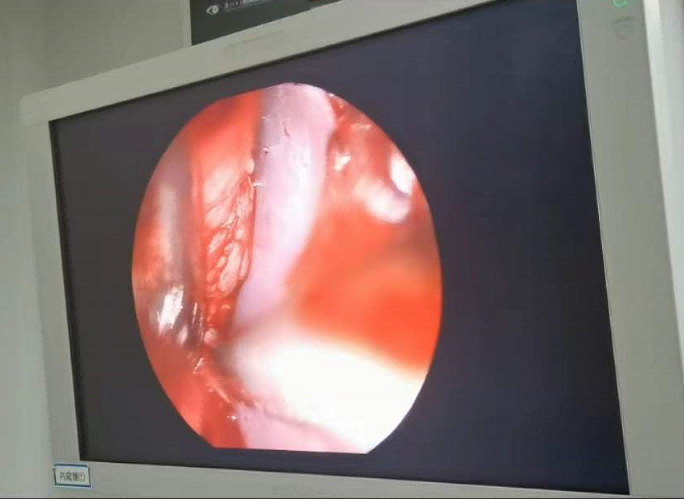

送到廈門眼科中心的時候,林老師受傷的左眼還在流血。眼整形科的鄧坤明副主任醫(yī)師緊急為他安排了“內(nèi)鏡下眶骨折修補+鈦網(wǎng)鈦釘植入術”。

圖為:內(nèi)鏡下眼眶骨折修補術

手術過程中林老師還出現(xiàn)了驚險的眼球后大出血,還好鄧坤明于緊急之中穩(wěn)住了病情,并順利完成了手術。術后第二天,林老師的術后反應就很輕,恢復良好,他一邊感謝著鄧坤明的“救命之恩”,一邊自嘲著自己示范了個“反面教材”。